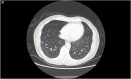

Whole-genome sequencing identifies nosocomial transmission of extra-pulmonary M. tuberculosis